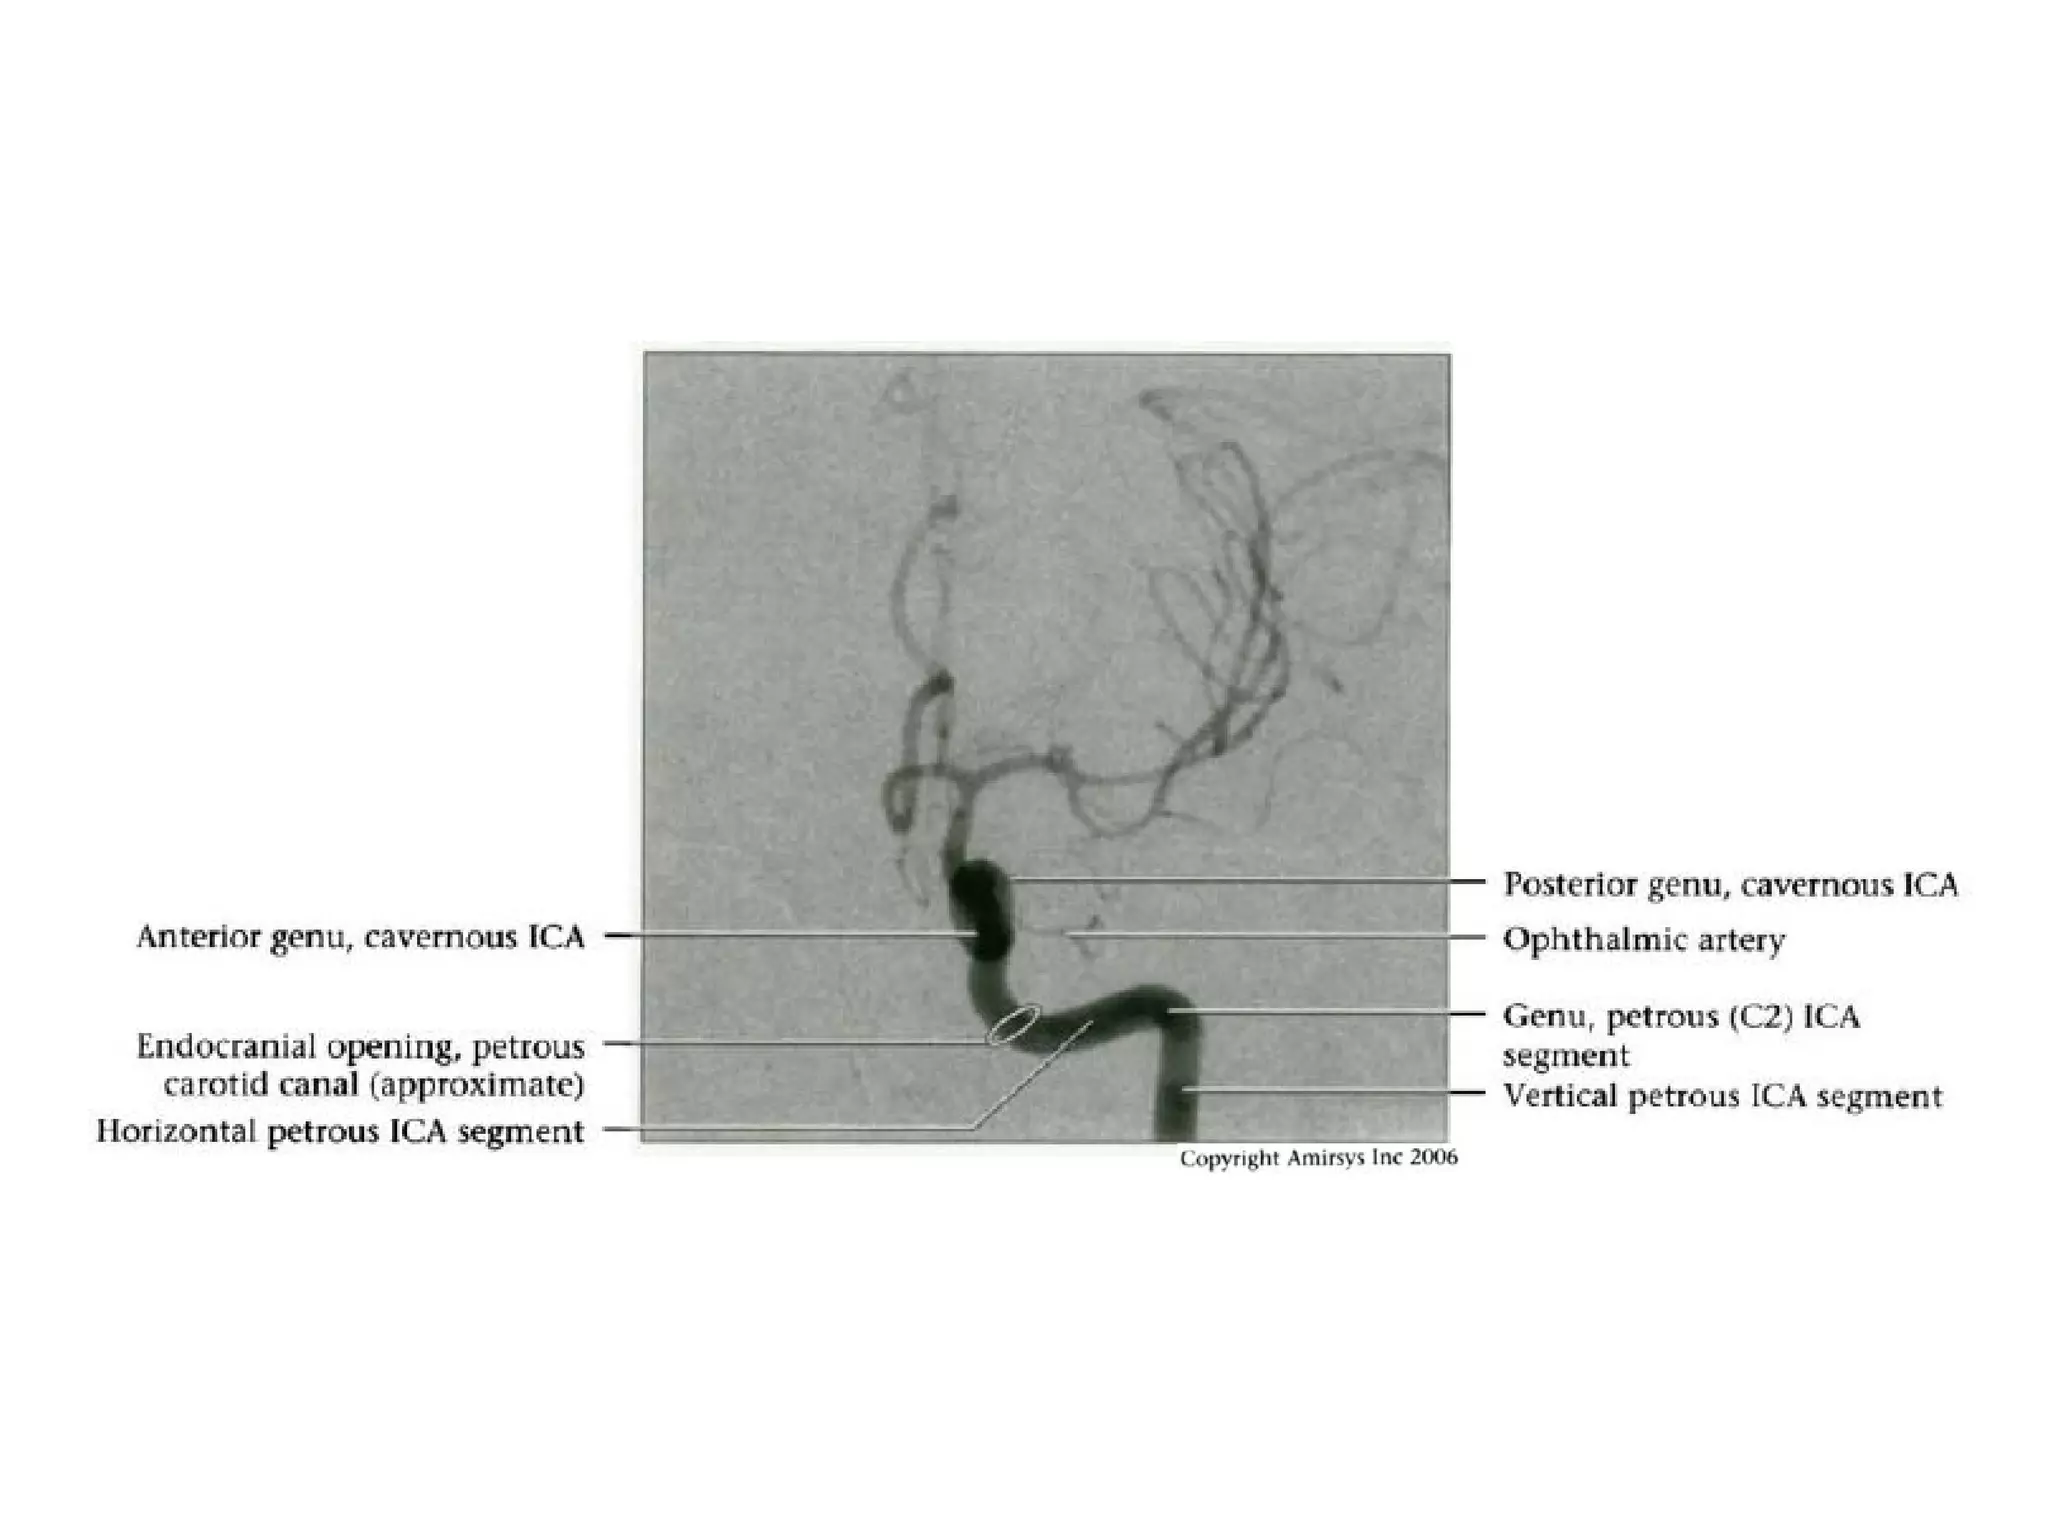

INTRACRANIAL INTERNAL

CAROTID ARTERY

Overview

• Complex course with several vertical /

horizontal segments, 3 genus (one

petrous, two cavernous)

• Six intracranial segments (Cervical lCA =

C1):

- Petrous (C2), Lacerum (C3),

Cavernous (C4), Clinoid (C5),

Ophthalmic (C6), Communicating (C7)

Petrous (C2) segment

• Contained within carotid canal of temporal bone

- Surrounded by extensive sympathetic plexus

- Two C2 subsegments joined at genu

• Short vertical segment - anterior to internal jugular vein

(lJV)

• "Genu" (where petrous ICA turns anteromedially in front

of cochlea)

• Longer horizontal segment

- Exits carotid canal at petrous apex

- Branches

• Vidian artery (artery of pterygoid canal)

anastomoses with external carotid artery (ECA)

• Caroticotympanic artery (supplies middle ear)

Cavernous (C4) segment

• Three subsegments joined by two genus (knees)

- Posterior vertical (ascending) portion

- Posterior (more medial) genu

- Horizontal segment

- Anterior (more lateral) genu

- Anterior vertical (subclinoid) segment